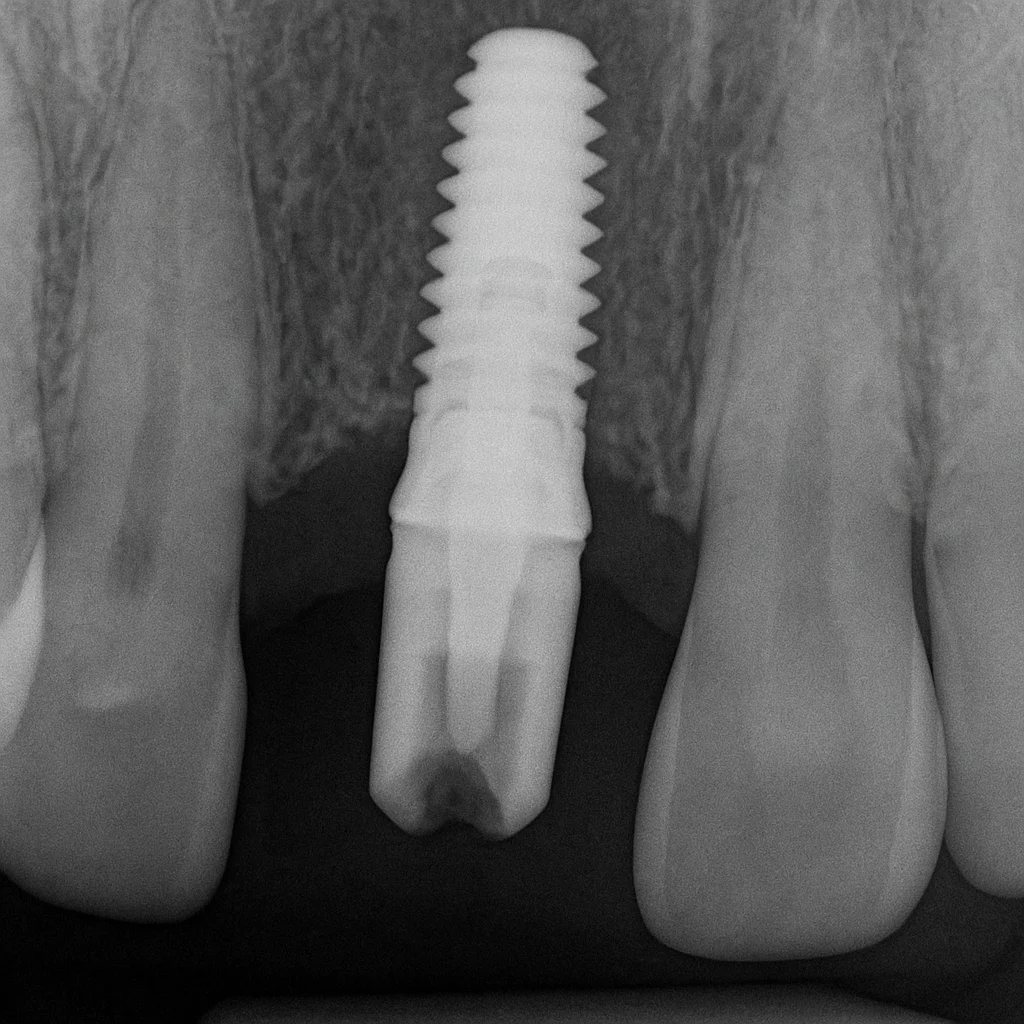

Cosa significa “innesto osseo non riuscito”

Un innesto osseo è una procedura chirurgica eseguita per aumentare il volume dell’osso mascellare o mandibolare, al fine di poter inserire un impianto dentale stabile e duraturo. Può essere realizzato con:

Si parla di innesto osseo non riuscito quando, a distanza di settimane o mesi, il materiale innestato non si integra correttamente con l’osso naturale del paziente. In pratica, non avviene la rigenerazione ossea desiderata e l’area rimane debole o insufficiente per sostenere un impianto dentale.

Quando l’impianto dentale non attecchisce

La mancata osteointegrazione è la condizione in cui l’osso non si lega all’impianto in titanio. Può essere causata da:

Se l’impianto non attecchisce, spesso è necessario rimuoverlo e rigenerare nuovamente l’osso.